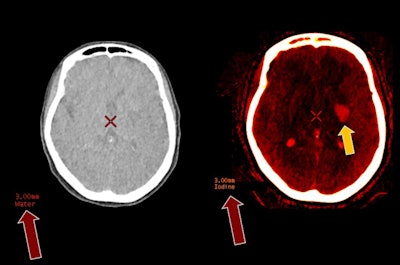

- Brain -- Dual-energy CT is particularly valuable for differentiating between hemorrhage and contrast extravasation in patients who have had strokes. It also reduces metallic and beam-hardening artifacts.